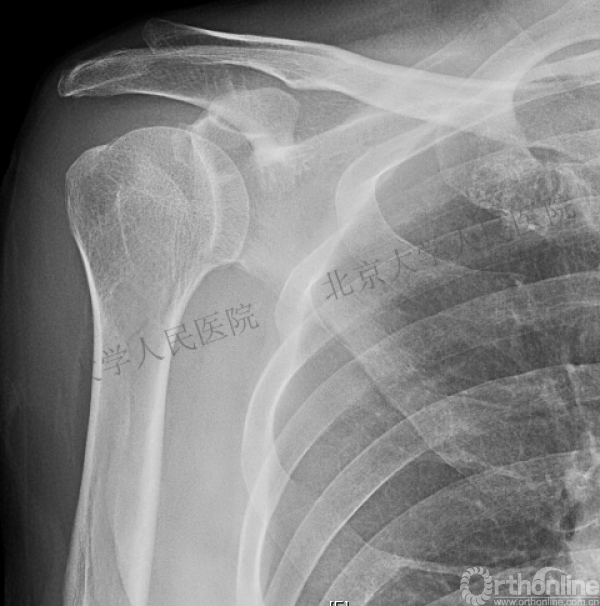

我们接诊的病人:谷××,男,61

一过性意识丧失,右肩疼痛伴活动受限14小时入院

(一)查体:右肩关节肿胀,前方空虚,喙突凸起可触及。后方饱满,可触及肱骨头。局部压痛明显,活动受限。右手拇指指尖部轻度麻木,末梢血运良好。

X线检查

(二)目前诊断:

1.右肱骨近端骨折

2.右肩关节后脱位